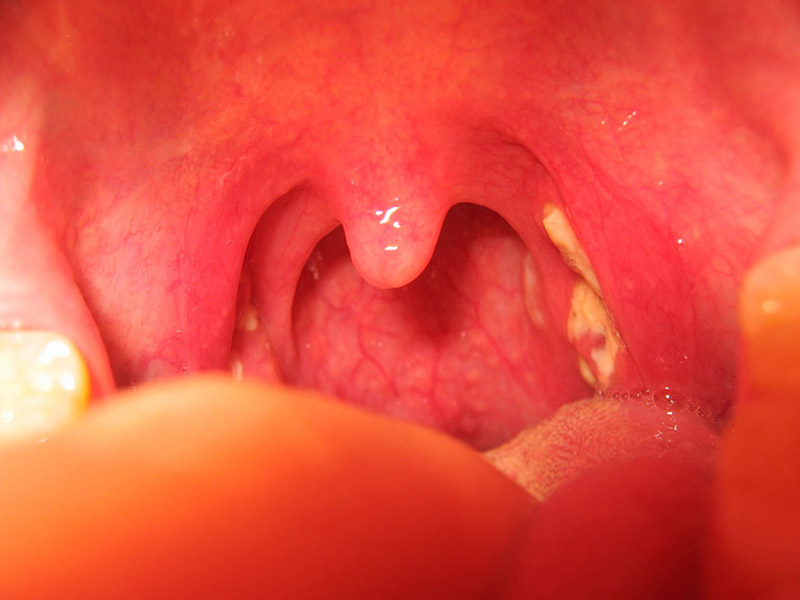

Viêm amidan hốc mủ là triệu chứng viêm nhiễm cấp tính hay mãn tính do vi khuẩn gây nên, nếu như không được điều trị kịp thời sẽ dẫn đến rất nhiều biến chứng nguy hiểm, nguyên nhân gây nên tình trạng này là gì? Điều trị có khó không hãy cùng tìm hiểu cùng […]